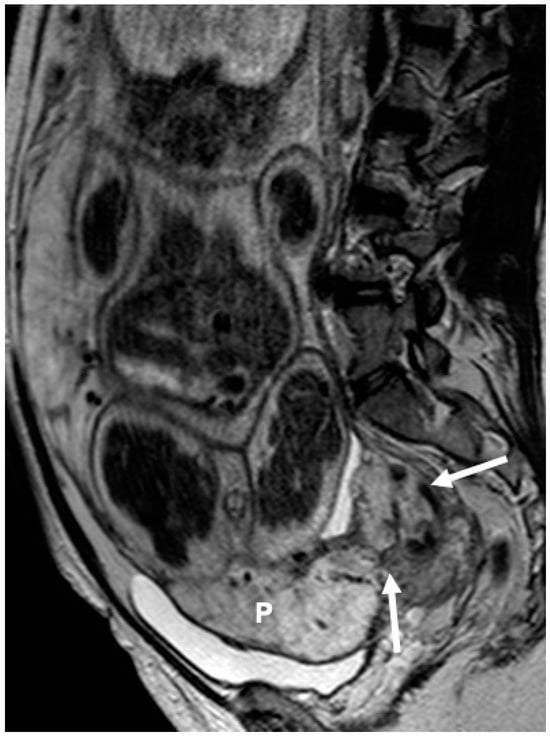

2.2. MRI Protocol

2.3. Image Interpretation